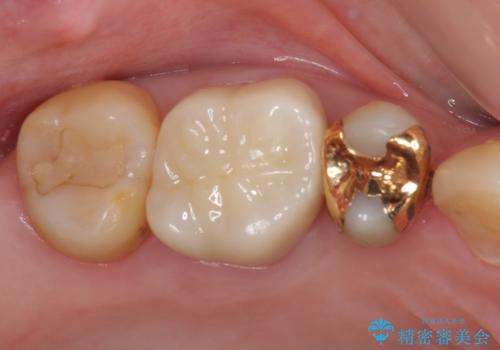

一部歯肉の中にまで虫歯が波及しており、汚れが溜まりやすくなっていましたが、クラウン装着後は汚れが溜まることはなくなりました。

しみていた症状もなくなり、患者様には大変満足していただきました。